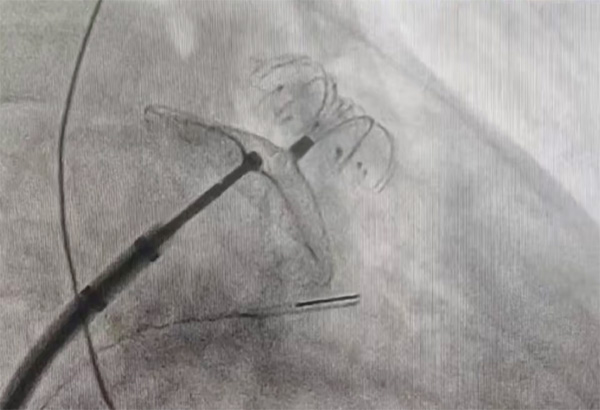

植入过程:释放封堵盘后造影可见下缘存在少量残余分流,通过超声观察为靠近二尖瓣位置贴靠不佳,但术中评估钢缆拉力明显,预估释放后能够有效贴合,牵拉15s无位移,可以释放。

释放过程:释放封堵器的过程能够看到明显贴靠,通过造影发现先前的残余分流消失,未见新增的残余分流。

通过超声可见封堵器外盘形态良好,未见明显残余分流;可再行房间隔缺损封堵术。

房缺封堵器植入后推拉稳定,形态良好,通过经胸彩超未见残余分流,遂释放封堵器。